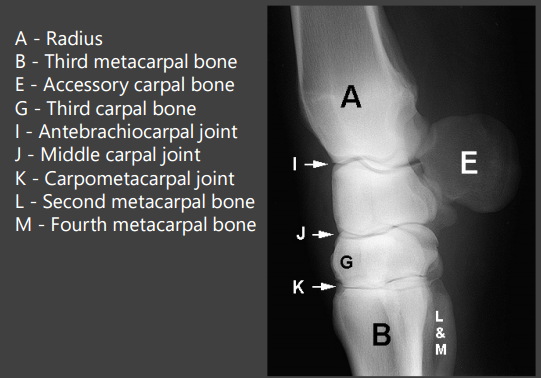

18

Q

A

Carpus:

A - Radius

I - Antebrachiocarpal joint

E - Accessory carpal bone

J - Middle carpal joint

G - Third carpal bone

K - Carpometacarpal joint

B - Third metacarpal bone

L - Second metacarpal bone

M - Fourth metacarpal bone